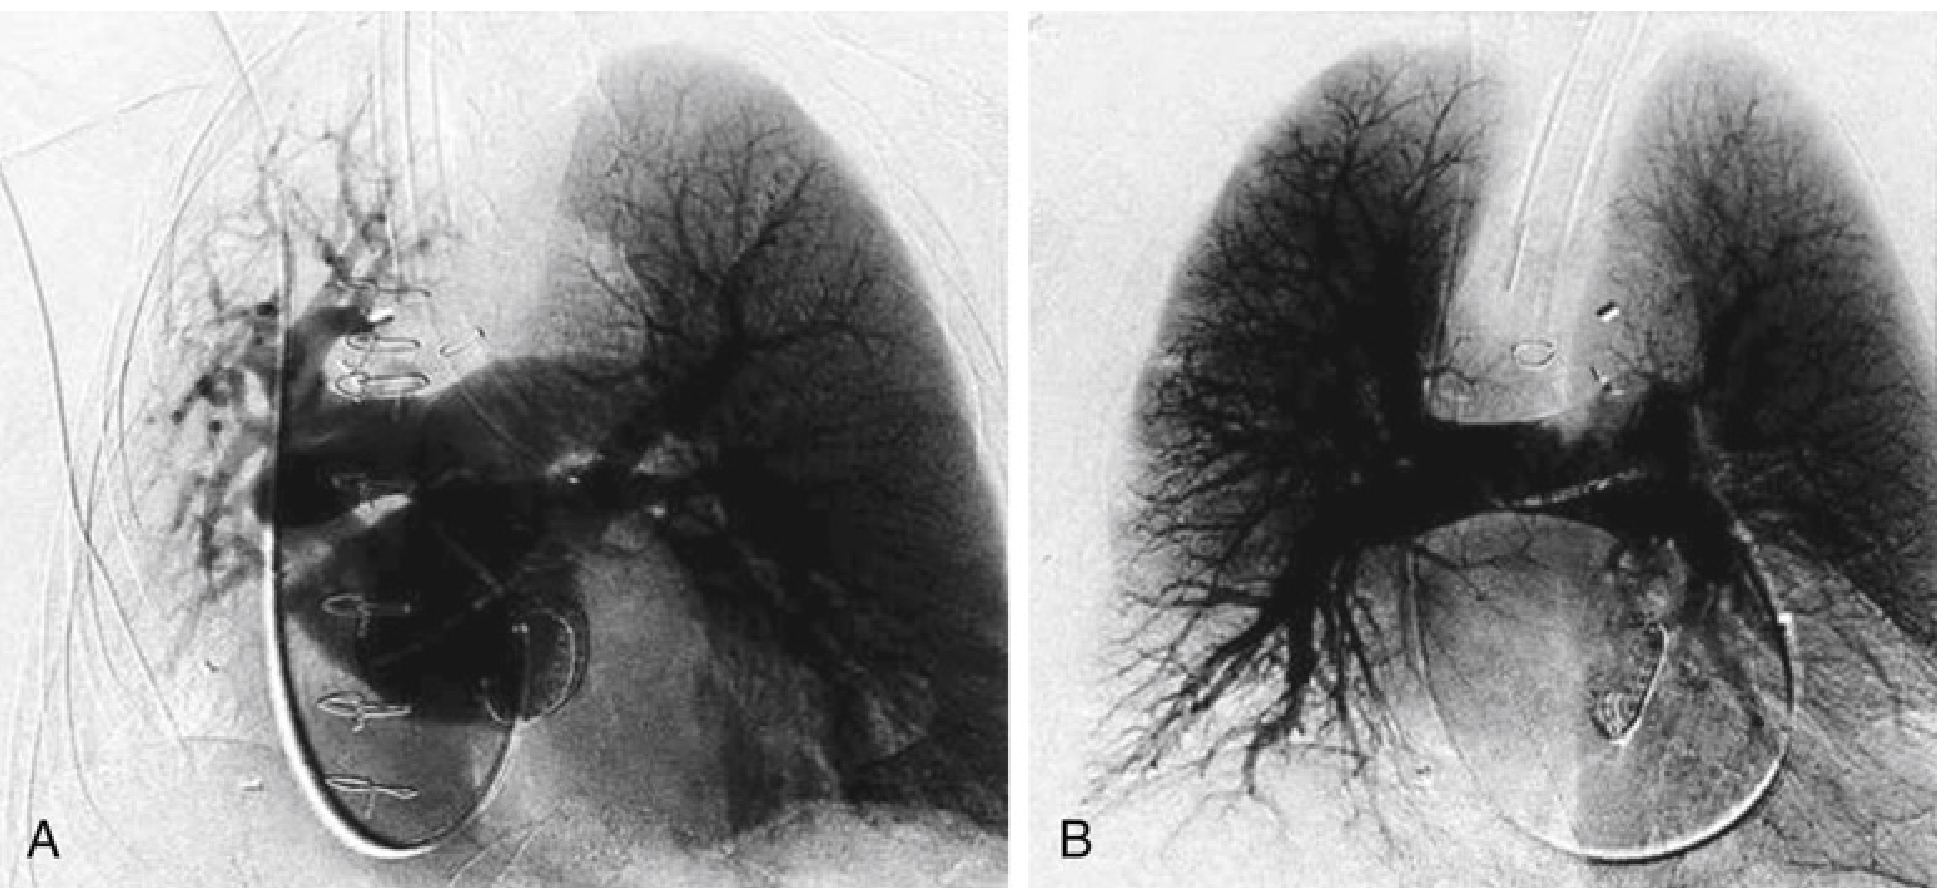

Pulmonary angiograms showing HPV during one-lung vs. two-lung ventilation

(A) During isolated left-lung ventilation: peripheral microvascular perfusion to the left lung only; no microvascular perfusion to the right (hypoxic) lung — demonstrating HPV. (B) Resuming two-lung ventilation: symmetric microvascular perfusion restored bilaterally. — Miller's Anesthesia, 10e (Royster et al., Anesthesiology 2022)